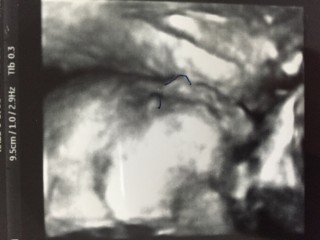

心臓のエコー写真。

右室・右房・左室・左房異常なし。